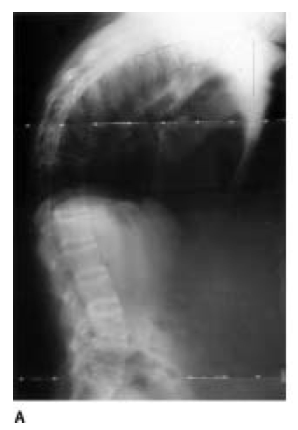

Diagnosis? Treatment?

Kyphotic Deformity from ank spond